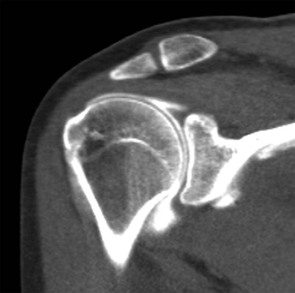

Computed arthrotomography of the shoulder was widely used prior to the development of MRI and for years was considered the gold standard in the imaging of labral abnormalities.17-19 The combination of CT with intraarticular injection of contrast material provides a highly sensitive method of evaluating the glenoid labra and articular cartilage.20,21 During the past two decades, MRI and MRA largely replaced CTA in the evaluation of rotator cuff abnormalities and glenohumeral instability.22,23 Recent reports of CTA performed with use of multidetector CT (MDCT) demonstrated accuracy equivalent to or better than MRA for proximal biceps tendon,24 anterior labral injury, and superior labral anterior to posterior (SLAP) lesions.8,25 It is especially useful in the evaluation of the shoulder in a patient with a contraindication to MRI. Axial, oblique sagittal, and oblique coronal reformatted images are obtained to provide a better evaluation of the rotator cuff and labrum and to provide the same reconstruction planes as MRI (Fig. 44-5).

Although MDCT arthrography clearly depicts full-thickness rotator cuff abnormalities and many of the lesions associated with glenohumeral instability, MRI and MRA improve sensitivity in the detection of interstitial and bursal-sided tears, tendinopathy, and bone marrow edema without using ionizing radiation. Relative to CTA, MRI and MRA provide superior soft tissue contrast. However, MDCT arthrography with submillimeter-thick source slices allows exceptional spatial resolution, which assists in the detection of labral tears and the visualization of cartilage lesions.